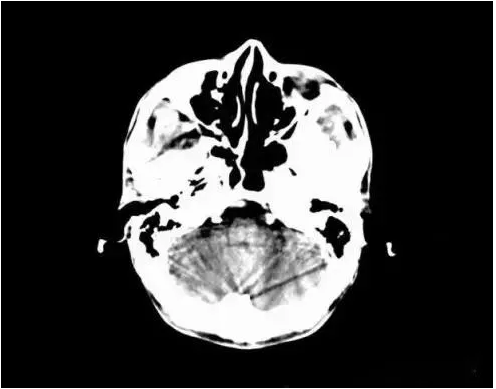

2.異物偽影:主要為密度差別極大的物體如金屬和人體組織一起掃描時所造成,偽影的特點是沿著高密度物體呈放射狀排列。有時圖像上不一定能直接看到目標異物,但只要仔細觀察偽影的放射狀搏列方向,即能找到異物的來源。

2、金屬異物偽影:金屬異物產生的放射狀偽影,嚴重時明顯影響診斷。在掃描前應去除病人體外隨帶的金屬物質,而病人體內無法去除的金屬物質,如假牙或牙內填充物、假肢、各類金屬支架等,可采用傾斜機架或掃描線的角度盡可能避開。目前也有研究采用某種算法抑制此類偽影。腹部常規掃描一般服溫開水,盡量不要服含碘造影劑。